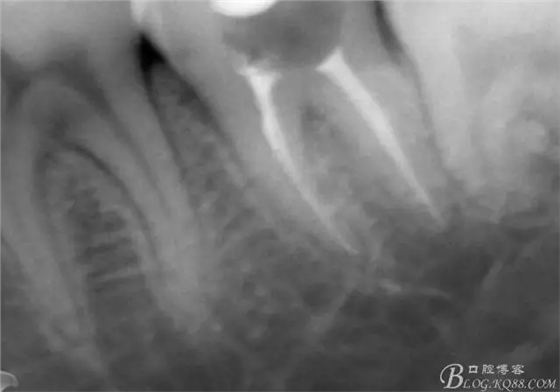

X線示牙膠尖到達工作長度,故行AH-PLUSH糊劑配合卡瓦熱牙膠機運用連續(xù)波充法根充,暫封拍根尖片。

第四次復(fù)診,37叩(—)。此次行冠部修復(fù),因涉及38的拔除,患者不愿拔除,與患者介紹修復(fù)材料與方法,擬37E.max嵌體修復(fù),術(shù)前常規(guī)簽修復(fù)知情同意書。